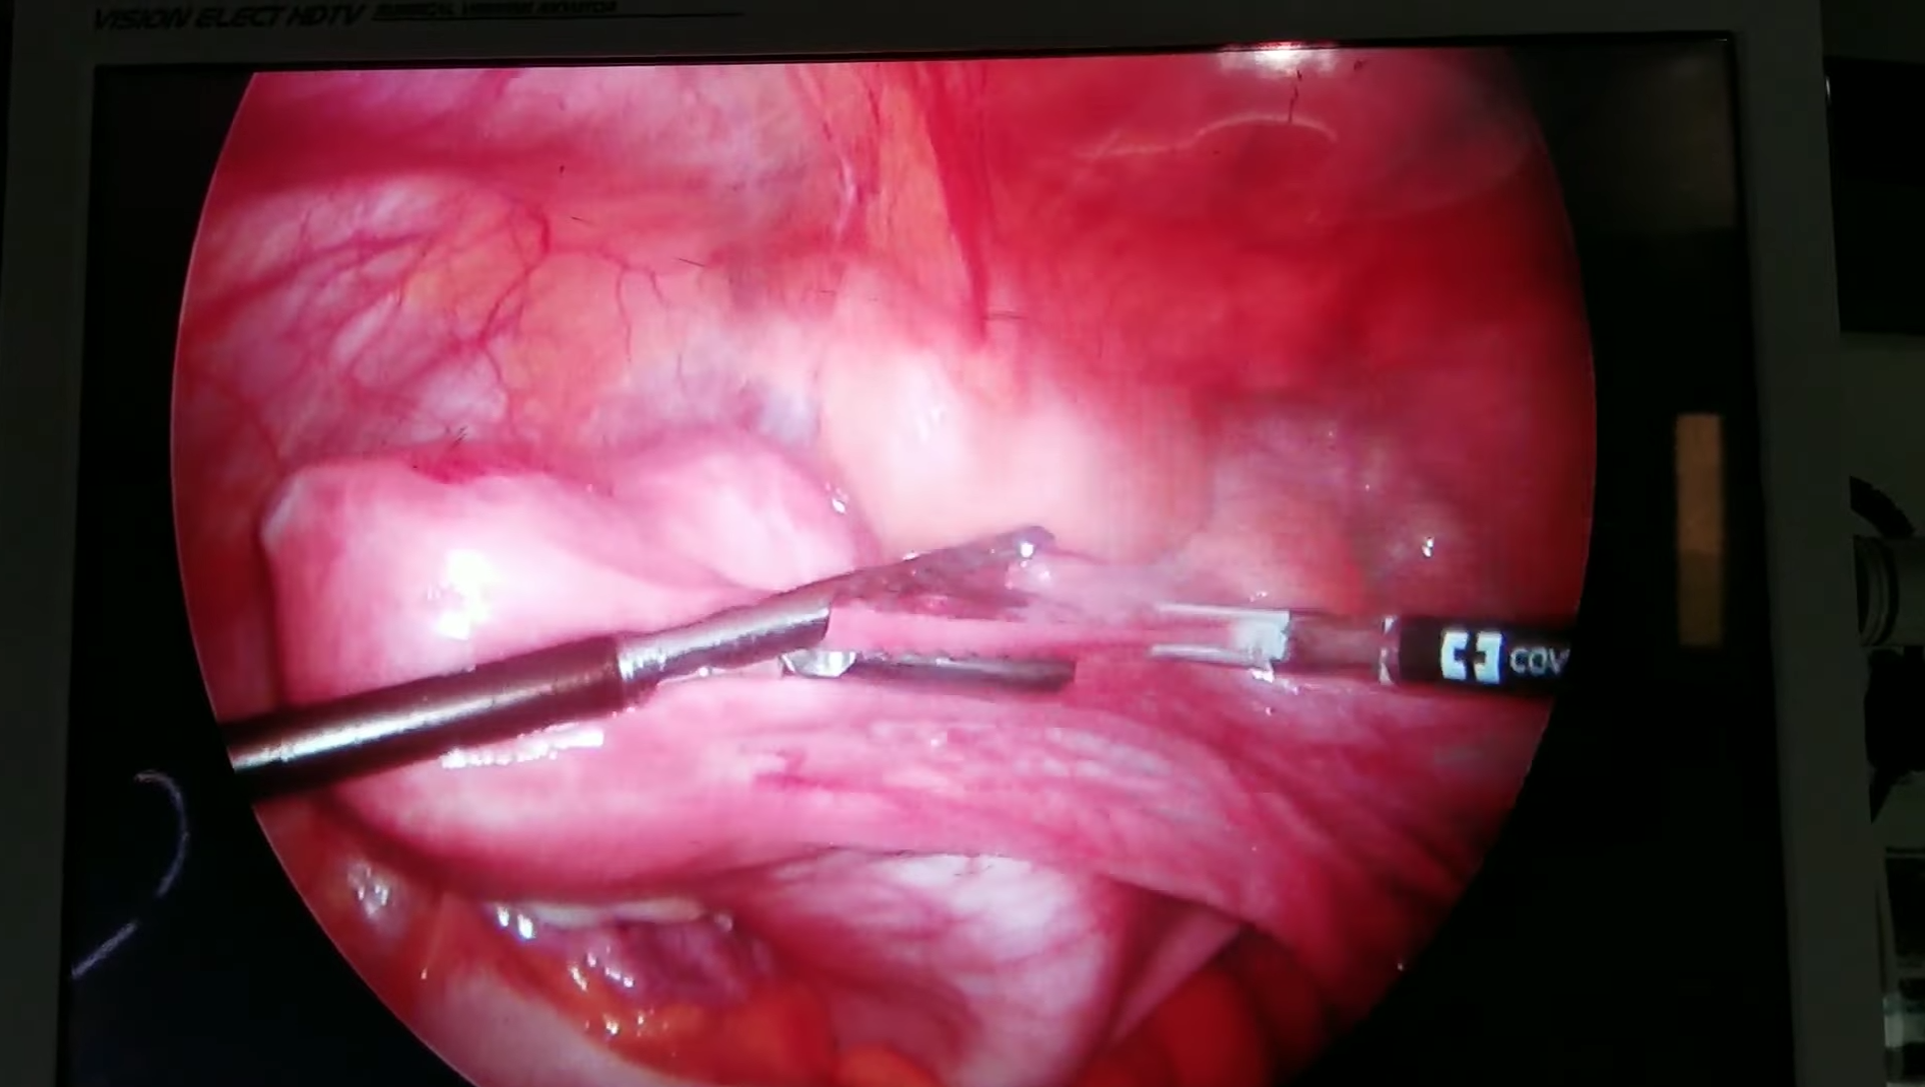

Cilt Grefti Uygulaması

Plastik Ve Rekonstrüktif Cerrahi

Ardian Kryeziu

Cilt Grefti Uygulaması

Plastik Ve Rekonstrüktif Cerrahi

Ardian Kryeziu

Cilt Grefti Uygulaması